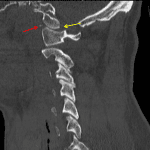

- Multiple tiny acute displaced fractures along the anterior aspects of both C1 superior articular facets with mild anterior subluxation of the occipital condyles relative to C1 and widening of the posterior aspect of both atlanto-occipital joints

- Widening of the C1-C2 interspinous interval and of the superior aspect of the sagittal atlantodental interval

- Extensive prevertebral edema extending from the skull base through the C5 level

Acute fracture-subluxation at the craniocervical junction with multiple tiny acute displaced fractures along the anterior aspects of both C1 superior articular facets, mild anterior subluxation of the occipital condyles relative to C1, widening of the posterior aspect of both atlanto-occipital joints, widening of the C1-C2 interspinous interval, and widening of the superior aspect of the sagittal atlantodental interval. MRI could further evaluate the extent of ligamentous injury.

Extensive upper and mid cervical prevertebral edema.